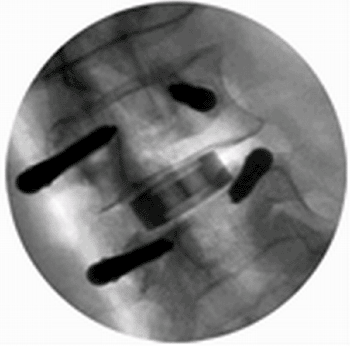

Patient Registration Mask Available for Portable CT

An innovative integrated surgical navigation unit offers surgeons better orientation in the OR and enables minimally invasive surgeries with higher accuracy. More...